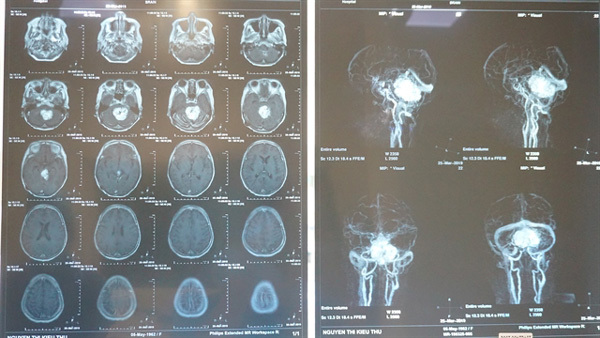

| The patient’s MRI showed brain stem glioma. Photo courtesy of the City International Hospital |

When hospitalised this time, doctors prescribed a blood analysis, biochemical analyses and an MRI investigation of the brain.

A pathological examination confirmed the diagnosis of hemangioblastoma in the left temporal lobe and the need for emergency surgical intervention. The surgery was done on March 31.